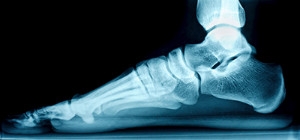

The medical term for flat feet is known as pes planus or pes valgus. The noticeable symptom of flat feet is a lack of an arch when the foot is lying flat on the ground. Most babies are born with flat feet and the arch typically develops with age. Research has indicated there are two types of flat feet. An arch that can be seen when the foot is elevated is known as a flexible flat foot and an absent arch also when the foot is elevated is known as a rigid flat foot. Flexible flat feet generally do not cause severe pain although some patients may feel mild achiness if intensely walking. Abnormal foot development may be the cause of rigid flat foot and surgery can be a necessary option for a significant correction. Some patients will even have a second surgery after the foot has fully formed to fuse the bones together. If you have flat feet, it is advised that you confer with a podiatrist.

If you suspect that you have flat feet, it is best to consult your podiatrist. Your foot doctor will examine the suspected foot and observe how it looks while you sit and stand. He or she may take an X-ray to determine how serious the condition is. Some common signs of flatfoot include toe drift, in which the toes and front part of the foot point outward, a short Achilles tendon, and a heel that tilts outwardly while the ankle tilts inward.